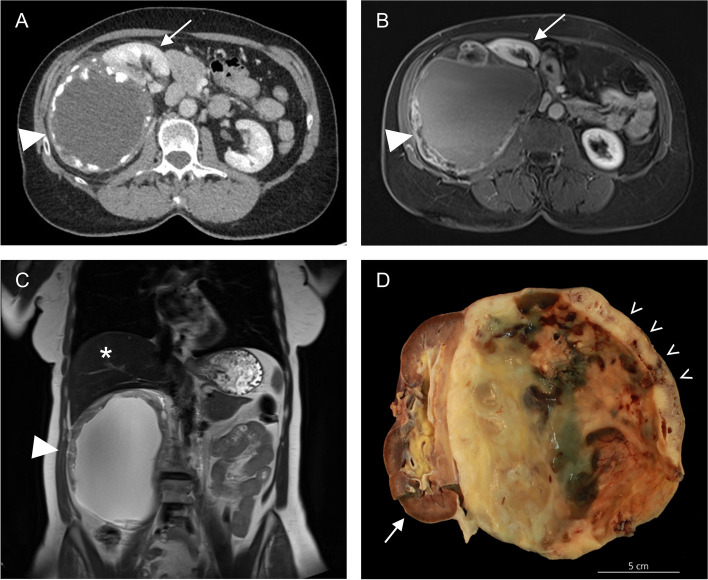

Background: Retroperitoneal dedifferentiated liposarcoma is a rare, aggressive malignancy, characterized by high rates of recurrences and the potential for metastasis. On imaging, these tumors typically present as a solid mass with lipomatous and non-lipomatous components. Cystic changes of dedifferentiated liposarcomas is exceedingly rare and might pose significant diagnostic challenges, with only a few cases reported in the literature. REPORT OF 2 CASES: We here present two cases of retroperitoneal dedifferentiated liposarcoma with a rare cystic presentation in two female patients aged 51 and 62 years. Imaging revealed large perinephric cystic masses measuring up to 13.0 cm and 16.1 cm, respectively, with calcifications of the cyst wall observed in the second case. Differential diagnoses included cystic echinococcosis, mesenchymal neoplasms, and benign cystic lesions (e.g. endometrial cyst). Both patients underwent upfront compartmental en-bloc surgical resection of the tumor mass and the kidney after multidisciplinary tumor board (MDT) discussion. Macroscopically, the tumors were adherent to but sharply demarcated from the kidney. Histological examination of the first case revealed a small component of well-differentiated liposarcoma (WDLPS) adjacent to a large non-lipogenic sarcoma with a prominent whirling pattern, compatible with dedifferentiation. The second case demonstrated a spindle cell neoplasm with prominent osteosarcomatous heterologous differentiation. MDM2 amplification was confirmed in both cases by molecular testing. No long-term follow-up data is available for either patient.

Conclusion: In conclusion, these cases highlight the importance of recognizing unusual and extensive cystic changes of dedifferentiated liposarcoma, which can complicate the diagnostic work-up.